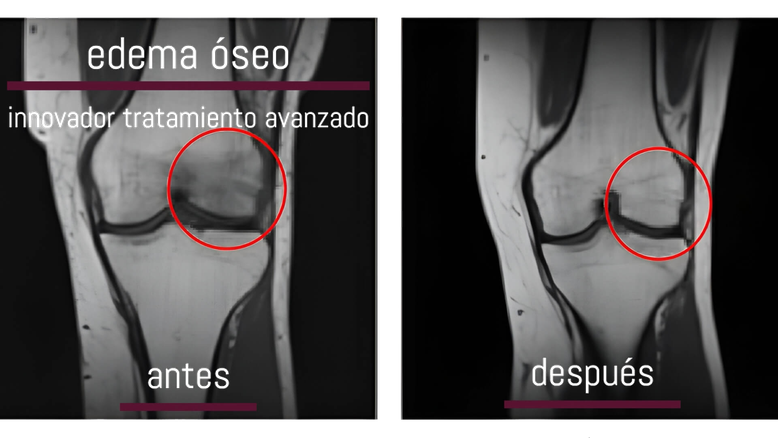

Edema óseo. Antes y después del tratamiento

Gracias a este avance tecnológico, los profesionales de Clínica San Javier podemos brindar a nuestros pacientes una opción de tratamiento efectiva y no farmacológica para combatir esta condición inflamatoria en los huesos y reducir hasta casi la mitad el tiempo de recuperación.

La fisioterapia también incluye modalidades de tratamiento fundamentales en la recuperación en esta patología como nuestro Sistema Super Inductivo con Magnetoterapia para aliviar el dolor y reducir la inflamación a la vez que acortamos los tiempos de recuperación hasta casi la mitad.